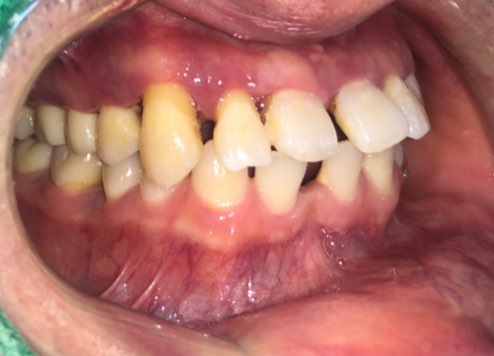

2-3달 만에 이정도로 공간이 없어지게 치아가 모아졌구요

화살표 되어있던 치아는 빼고 임시로 다른 치아를 붙여놓은 상태였습니다.

치아는 모아졌지만 아무래도 원래 본인 치아 모양이 있다보니 치아가 예쁜 모양은 아닙니다.